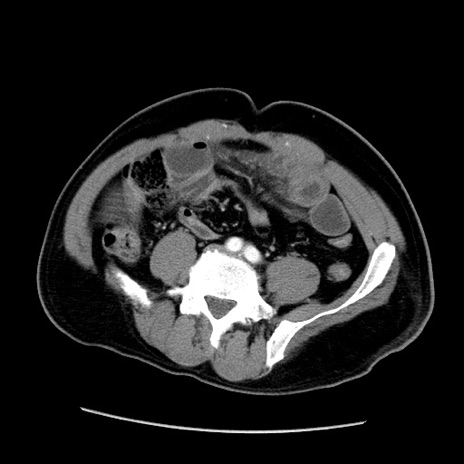

症例22(横断像)

【症例】50歳代男性

【主訴】腹痛

【現病歴】AVMからの被殻出血のため回復期リハ病棟入院中。 本日午後3時頃急に下腹部痛が出現した。

【既往歴】AVM、被殻出血、虫垂炎、高血圧

【身体所見】意識晴明、左半身不全麻痺、会話の理解は良好、36.5°C、腹部:膨隆、全体に板状硬、下腹部正中に圧痛点あり、反跳痛-、筋性防御不明、右下腹部にope scar

【データ】WBC 9400、CRP 0.06